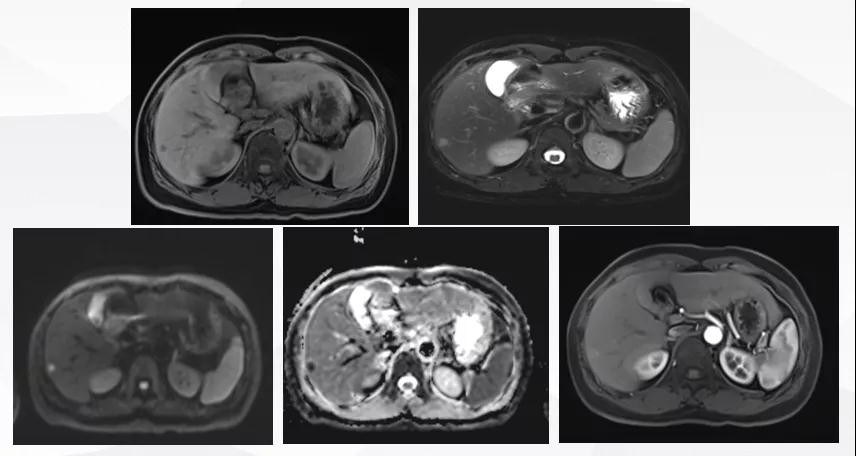

曲妥珠单抗辅助治疗结束6个月后,患者出现左侧胸部疼痛,ECT检查提示:左侧第4、5肋骨及T2胸椎转移;MR提示:T2椎体转移,肝S6段异常强化灶,考虑转移瘤可能性大;脑转移(图1)。

图1